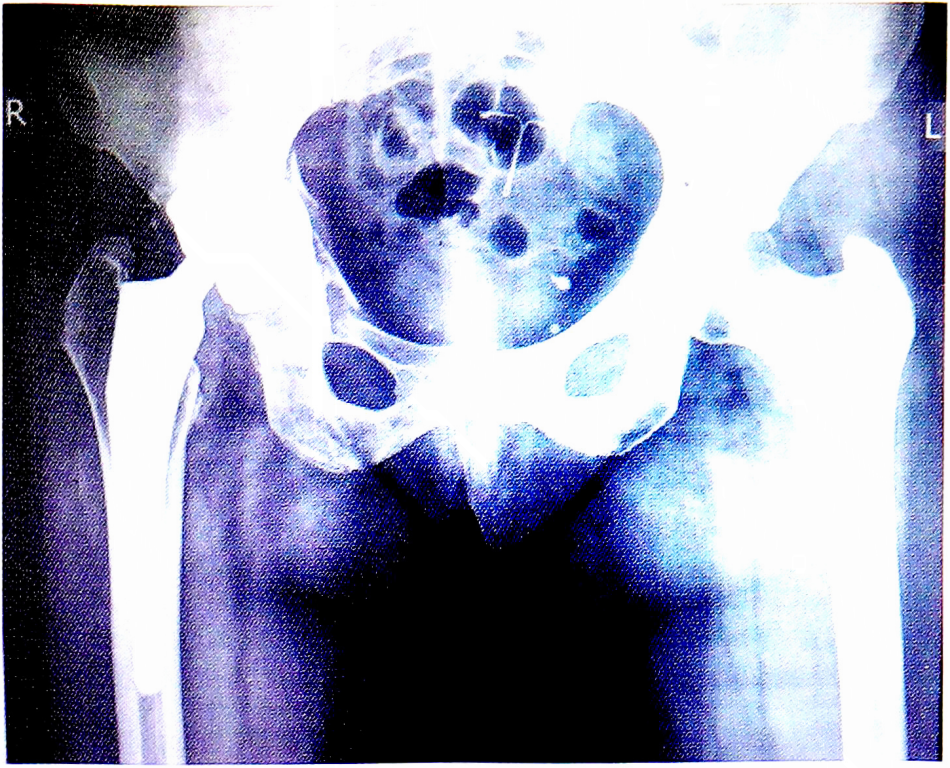

В феврале 2019 г. в отделение эндопротезирования НМИЦТО им. Н.Н. Приорова госпитализирована пациентка К.,44 лет, с диагнозом: нестабильность эндопротеза правого тазобедренного сустава. Первичное эндопротезирование выполнено в 2008 г. в другом учреждении, использован имплантат фирмы «Biomet М2а-Magnum» (бедренный компонент Тареrlос 12,5×145 мм, ацетабулярный компонент 52×46 мм, конический адаптер модульной головки 42-50 мм/-3 мм, модульная головка 46 мм). В 2013 г. пациентка упала, после чего появились и стали прогрессировать боли в области правого тазобедренного сустава. Длительное время за медицинской помощью не обращалась, лечилась консервативно без положительного эффекта. При осмотре выявлены укорочение правой нижней конечности до 2,5 см, ограничение движений в правом тазобедренном суставе и хромота при ходьбе. По данным лучевых методов исследования (рис. 1) определяются зоны резорбции вокруг вертлужного компонента эндопротеза, нарушение целостности кортикальной пластинки в области дна впадины и лонной кости. Выполнено ревизионное эндопротезирование правого тазобедренного сустава. При оперативном доступе обнаружены небольшой металлоз и выраженные рубцовые ткани. Жидкое содержимое отсутствовало. Бедренный компонент полностью покрыт костью, остеолиз вокруг него практически отсутствовал, при тестировании конструкция стабильна. При снятии модульной головки обнаружена техническая проблема — невозможность удалить адаптер головки вследствие его заклинивания («холодная сварка») на шейке бедренного компонента. Оригинальных инструментов [6] для удаления у нас не было, так как мы не работаем с производителем данного имплантата на постоянной основе, поэтому удалить адаптер не представлялось возможным. Затем был осуществлен доступ к ацетабулярному компоненту, подтверждена его нестабильность, смещение за счет остеолиза тела подвздошной кости и разворот вокруг собственной оси на 90°. После его удаления выявился выраженный костный дефект передней колонны и центра впадины (тип III В по Paprosky), прикрытый рубцовой тканью, но четко выделяющегося мягкотканного образования (псевдоопухоль) по типу «плюс-ткань» не обнаружено. Для замены ацетабулярного компонента при предоперационном планировании предполагалось использовать одну из двух техник: имплантировать соответствующий компонент методом «пресс-фит» с дополнительной пластикой костного дефекта танталовым аугментом или после пластики аллотрансплантатами («костные чипсы»), изготовленными в костном банке ЦИТО, установить антипротрузионное кольцо Burch-Schneider и цементный ацетабулярный компонент. В связи с нежелательностью увеличения травматичности оперативного вмешательства, что было бы неизбежно при удалении стабильного бедренного компонента, и степенью дефекта впадины, методом выбора стал второй вариант техники с использованием деталей ревизируемого эндопротеза — ацетабулярного компонента и модульной головки M2a-Magnum (при осмотре они не имели видимых повреждений на артикулирующих поверхностях). Произведена костная пластика дна и передней колонны впадины, имплантировано антипротрузионное кольцо Burch-Schneider (56 мм), в него на цемент установлен очищенный от рубцов и тщательно промытый антисептиками ацетабулярный компонент. На адаптер и с помощью импактора вновь установлена модульная головка, после чего произведено ее вправление (рис. 2).

Рис. 1. Рентгенограмма пациентки К.,44 лет при поступлении в НМИЦ ТО.

Fig. 1. X-ray of patient К.,44 years old at admission to NMITS TO.